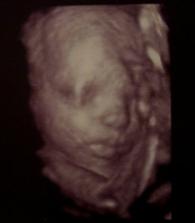

... v srpnu 2009 jsme se s manželem rozhodli, že necháme "rozrůst" naší rodinu...hned v půlce září 2009 mi vyšel 1. těhotenský test a nám, dvěma nepřipraveným, ale šťastným, se rozjíždí radostné šílenství jménem TĚHOTENSTVÍ ...